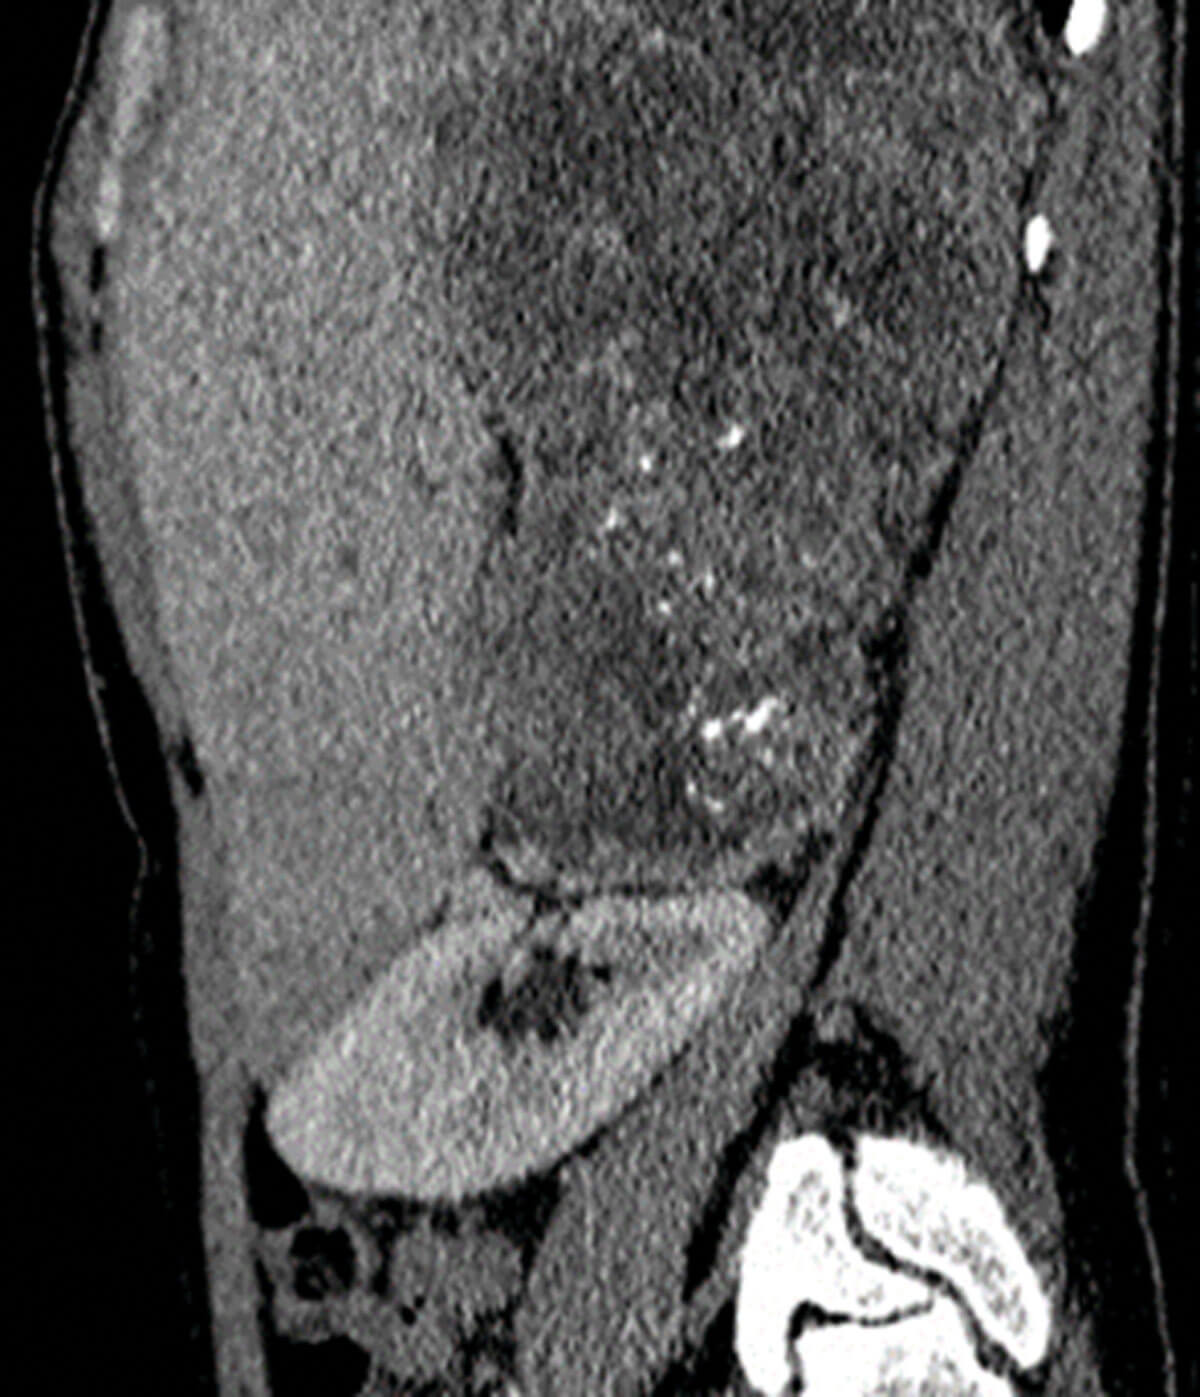

Figure 4: Sagittal post contrast CT showing a large and heterogenous mass arising from the right adrenal gland proven to be adrenocortical carcinoma on histology.